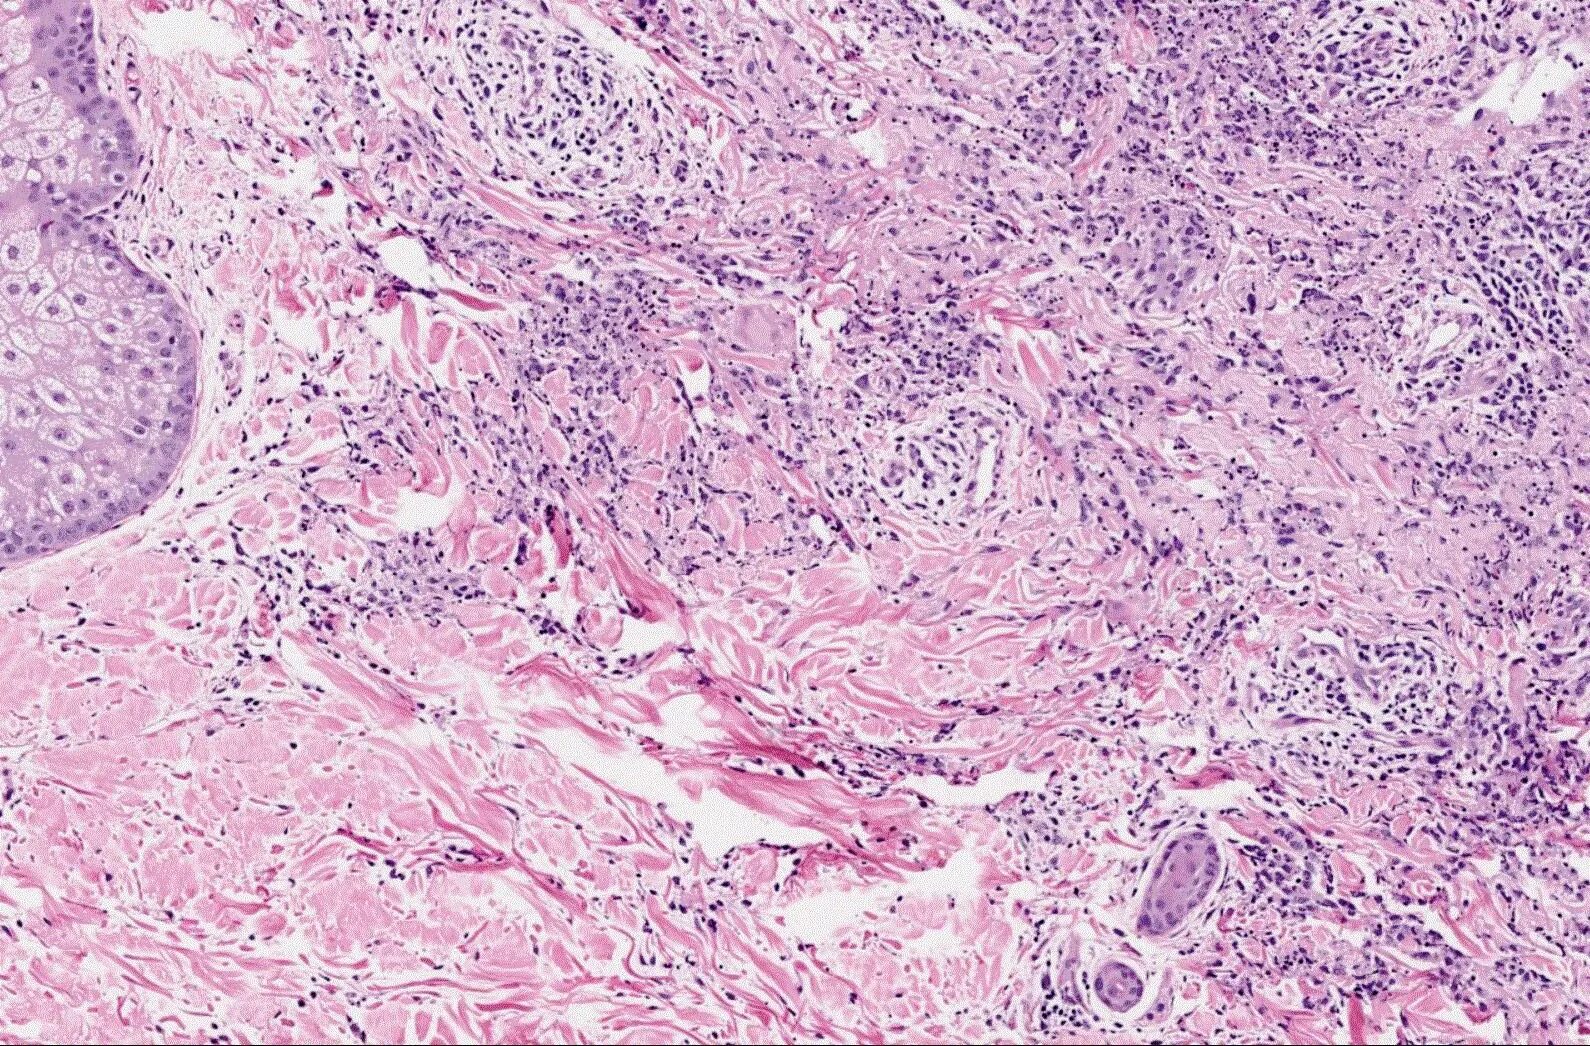

Гистология фото